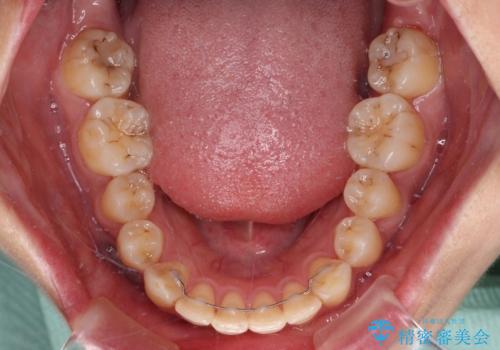

奥歯の咬み合わせはしっかりと改善され、前歯の突出感も改善されました。

- 1年5ヶ月